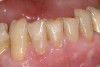

Figure  4  Possibly a combination of erosion and abrasion.

Figure 4